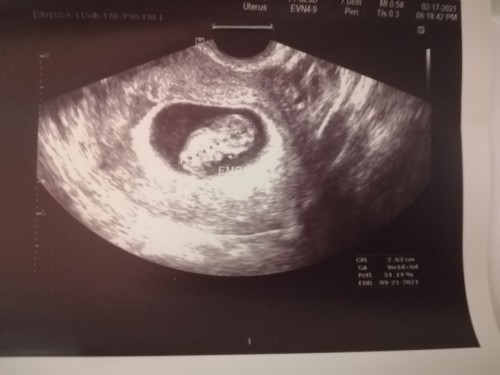

No gestational sac. Only thickened endometrium lang ang nakita at 1st ultrasound. 5 weeks ako nun based on my LMP. pinabalik ako ng ob ko sa 10th week ko. At nakita na sya wakas. 9 weeks and 1 day pa sya. Sa mga 1st time nagbuntis jan at same yung story sa akin. dont worry. Pray lang always kasi magpapakita talaga yan sya. #firstbaby #1stimemom